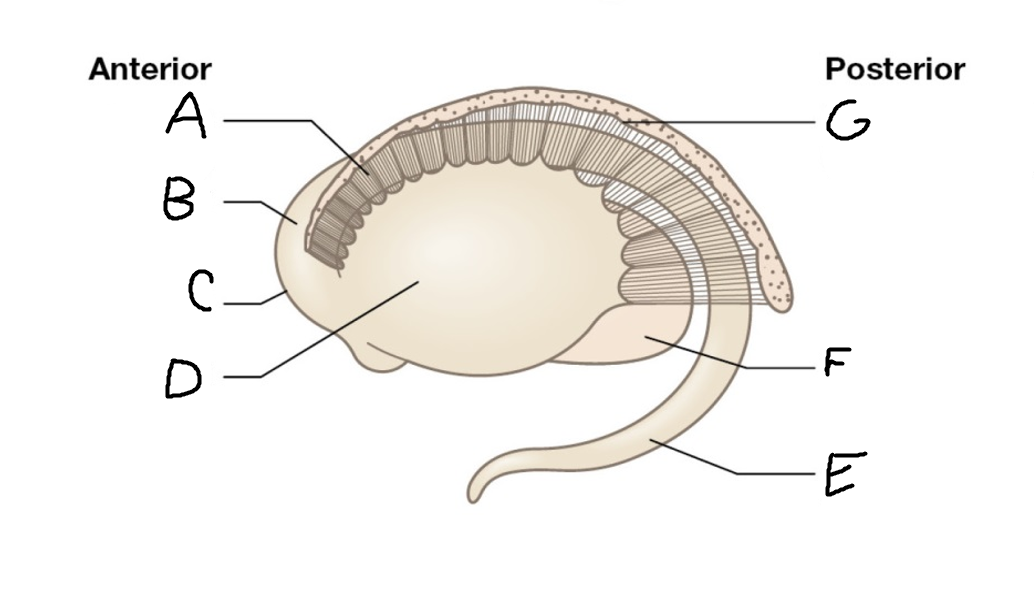

A

caudate nucleus head

C

caudate tail

D

globus pallidus (internal segment)

E

globus pallidus (external segment)

F

putamen